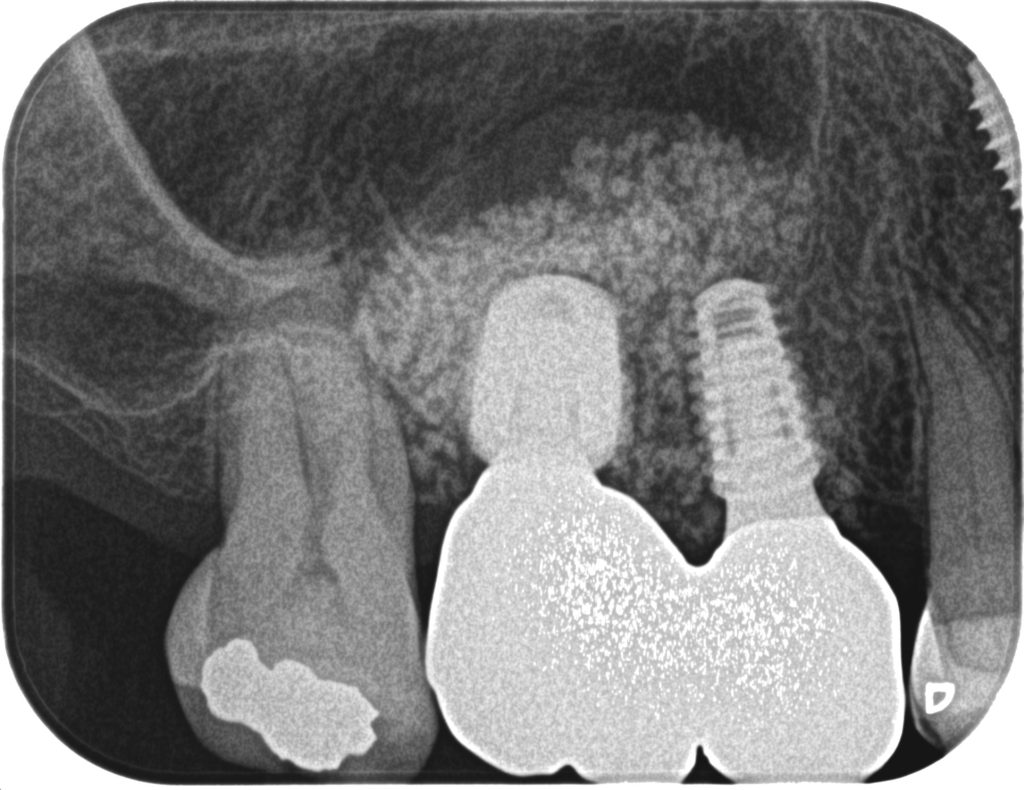

症例360代 男性 奥歯で噛めない 昔、義歯を作製したが煩わしく入れていない

治療前

治療後

治療前

治療後

治療前

治療後

治療前

治療後

左右大臼歯部は、残存骨が1~2㎜程度であったが、共にソケットリフト(上顎洞洞底膜挙上術)を行いインプラントを埋入。

約5ヶ月間の治療期間を経て、全てジルコニアを装着し終了。

リスクとしては外科的侵襲がある。デメリットは、保険外診療の為、経済的負担がある。

費用 187万(税込)(オペ・仮歯・最終補綴物まで含む)